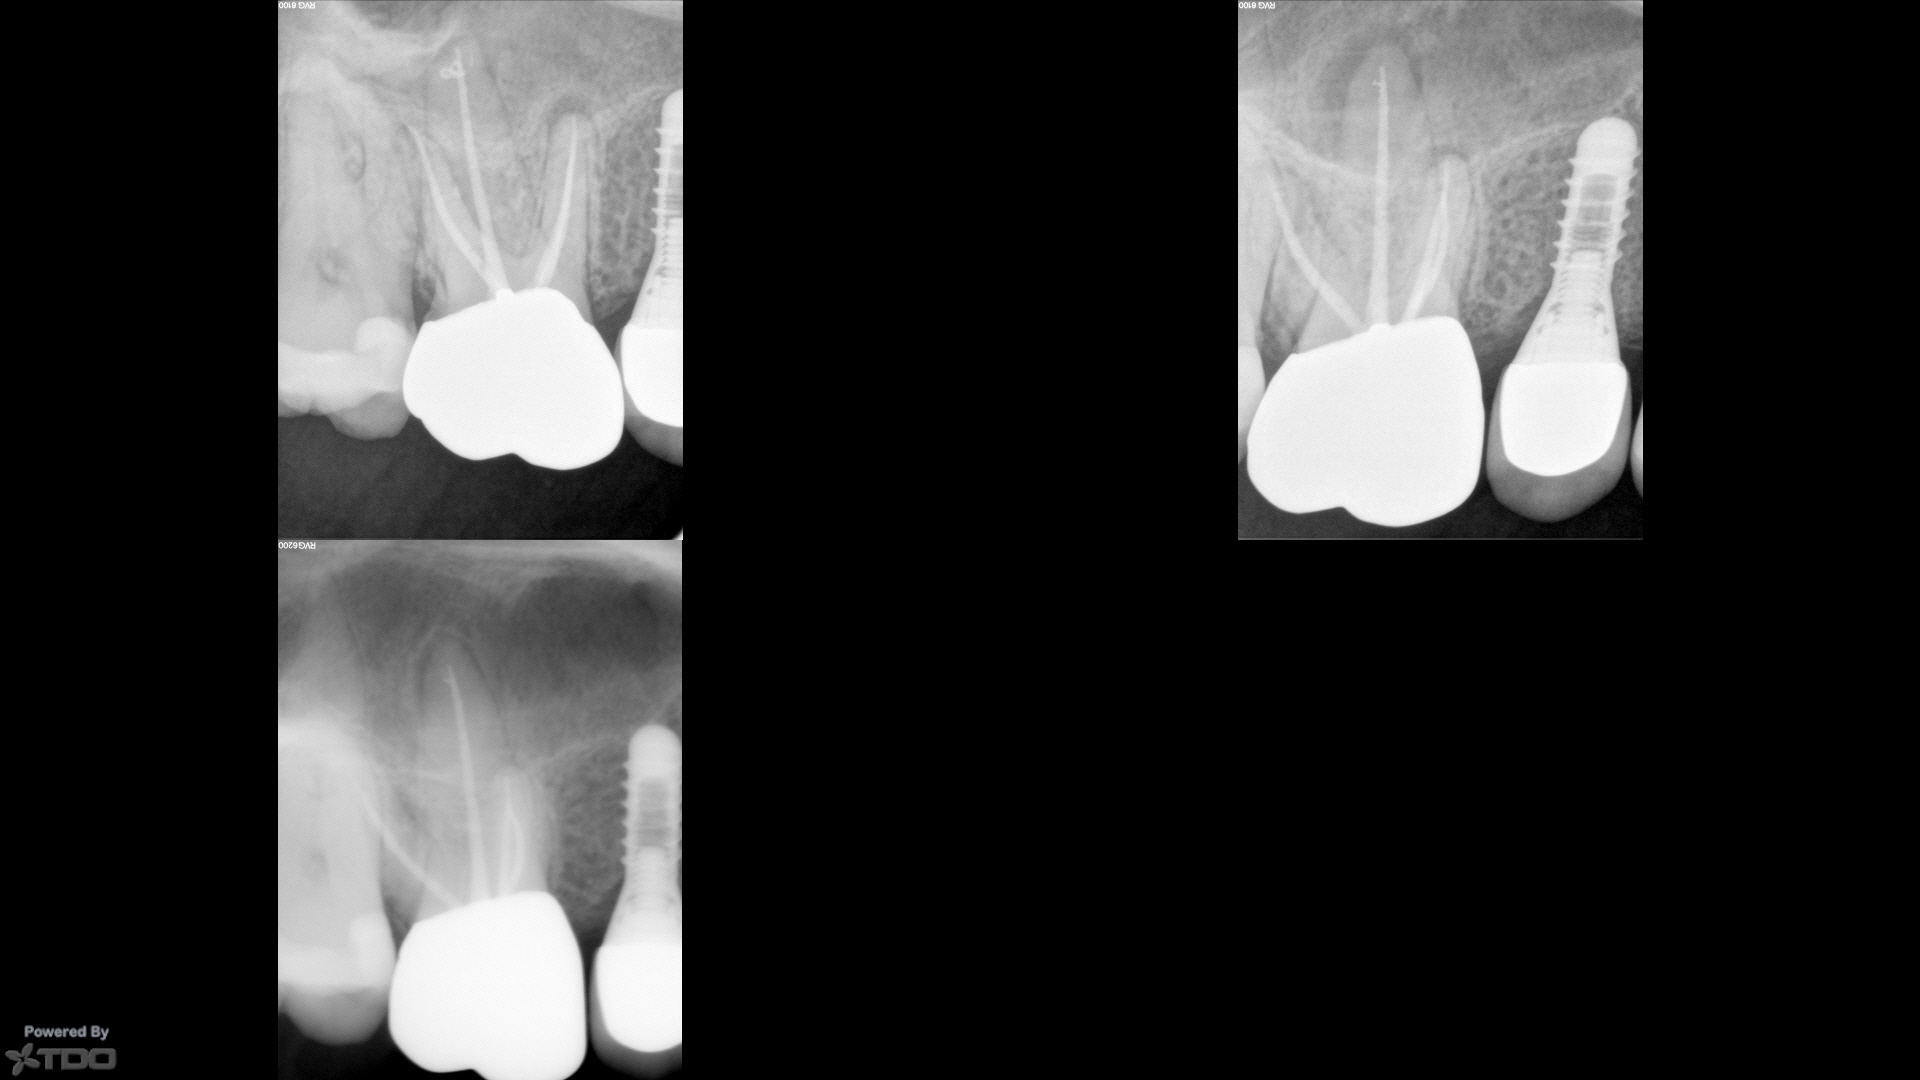

I don’t know, but I suspect it is “occlusion.” That is…I think the role of “occlusion” in AP is not under-appreciated, but unappreciated. I would ask that you observe all the broken-off teeth that come into your office with GP exposed, and they rarely have any symptoms, and also rarely have radiographic evidence of AP. There was a case report many years ago of a lower molar that had significant findings that went unaddressed, and then a followup with reduced findings. What one notices in that case was that the coronal portion of the tooth was largely missing, and thus was not likely to be in significant function.